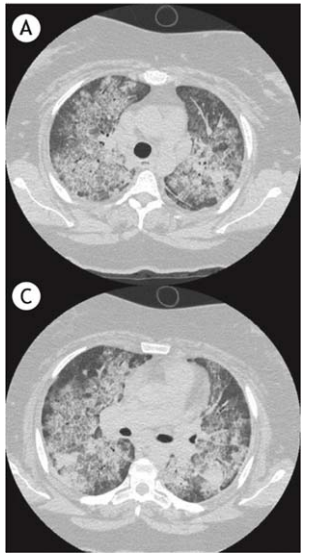

Um homem de 44 anos de idade, portador de IC há dez anos, em uso regular de furosemida (40 mg por dia), espironolactona (25 mg por dia), losartana (50 mg por dia) e amiodarona (400 mg por dia), em razão de episódio de taquicardia ventricular sustentada há três anos, ao exame físico, mostrava-se em estado geral regular, com tosse não produtiva, dispneia e ausência de febre, FR de 18 irpm, sat. de O2 de 97% em ar ambiente, FC de 54 bpm e PA de 130 x 90 mmHg, bilateralmente. Foi iniciado um tratamento para insuficiência cardíaca descompensada e introduziu-se ceftriaxone para a infecção pulmonar. Não houve melhora com essas condutas. Realizou-se um estudo tomográfico (mostrado a seguir) e uma biópsia transbrônquica, que mostrou pneumonia intersticial crônica não específica, com moderado infiltrado inflamatório mononuclear no septo alveolar e abundante número de macrófagos nos espaços alveolares.